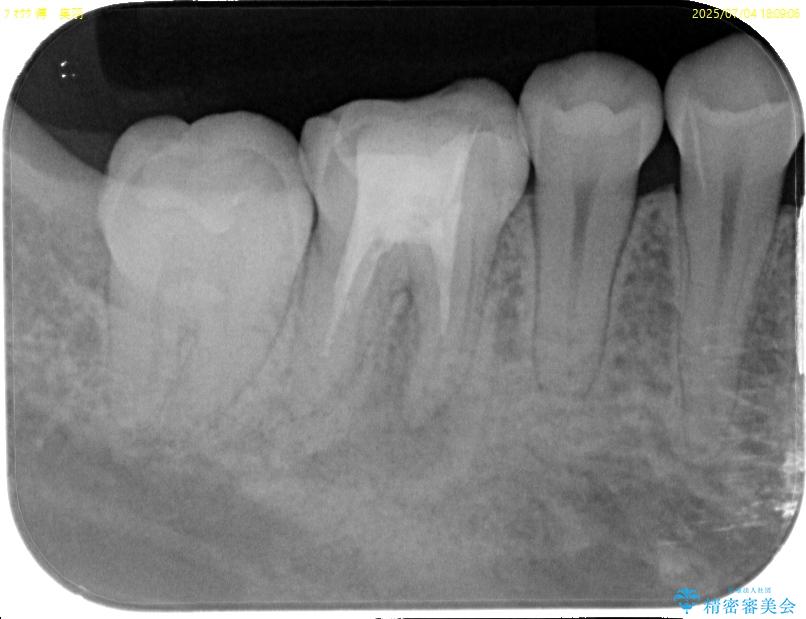

「以前に根管治療をした歯が、噛むと違和感がある」とのことでご来院された患者様の症例です。 患者様は、数年前に他院で根管治療を受けたとのことでしたが、被せもの(クラウン)は装着されていない状態でした。 噛んだときの違和感が慢性的にあり、食事中も気になるとのことで当院にご相談いただきました。 レントゲン検査では、根の先端に透過像(根尖病変の可能性)が見られ、過去の治療ではラバーダム防湿が使用されていなかったそうです。

当院ではラバーダム防湿をし、根管内の感染源をしっかりと除去するために再根管治療を行いました。

その後、ファイバーコア(グラスファイバー製の支台)を築造し、最終的には精密な適合性と審美性に優れたオールセラミッククラウンによる補綴をしました。